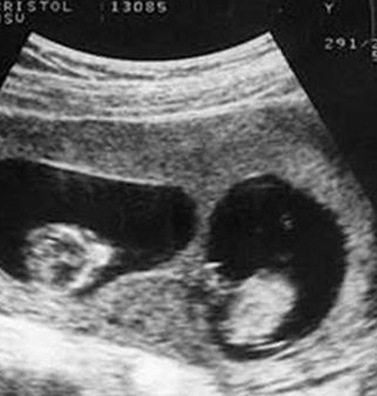

Khi đi siêu âm, Tiểu Mai được bác sĩ thông báo sẽ sinh đôi.

Trong thời ḱ đầu mang thai, Tiểu Mai, 25 tuổi, người Trung Quốc đi siêu âm và bác sĩ thông báo cô đang mang trong ḿnh thai sinh đôi. Bác sĩ có dặn cô tháng sau tới siêu âm định kỳ nhưng v́ bệnh viện ở xa nhà nên Tiểu Mai không tới khám lại nữa.

Trong quá tŕnh mang thai, Tiểu Mai chỉ đi khám 3 lần và sinh con ở tuần thứ 37. Cả gia đ́nh đều chuẩn bị sẵn tâm lư vui mừng để đón 2 đứa trẻ chào đời nhưng sau khi đưa được hai em bé ra ngoài, các bác sĩ nh́n thấy một đôi chân nữa trong bụng Tiểu Mai, họ lập tức đón em bé thứ 3 ra ngoài trong sự ngỡ ngàng.

Không phải 2 mà là 3 đứa trẻ trong bụng Tiểu Mai.

Trên thực tế, Tiểu Mai đă mang thai 3 đứa trẻ, 2 trai 1 gái nhưng khi siêu âm bác sĩ không hề thấy sự hiện diện của đứa trẻ thứ ba nên đă đưa ra kết luận là sinh đôi. Các bác sĩ cũng cho biết, có thể 2 thai nhi kia đă nằm chắn thai nhi thứ 3 nên khi siêu âm không nh́n thấy được. Thật may mắn, đứa bé thứ 3 ra đời rất khỏe mạnh. Vậy là niềm vui của gia đ́nh lại được nhân lên khi mà đáng lẽ họ chỉ có 2 đứa con th́ giờ lại xuất hiện thêm một thiên thần nhỏ thứ 3.